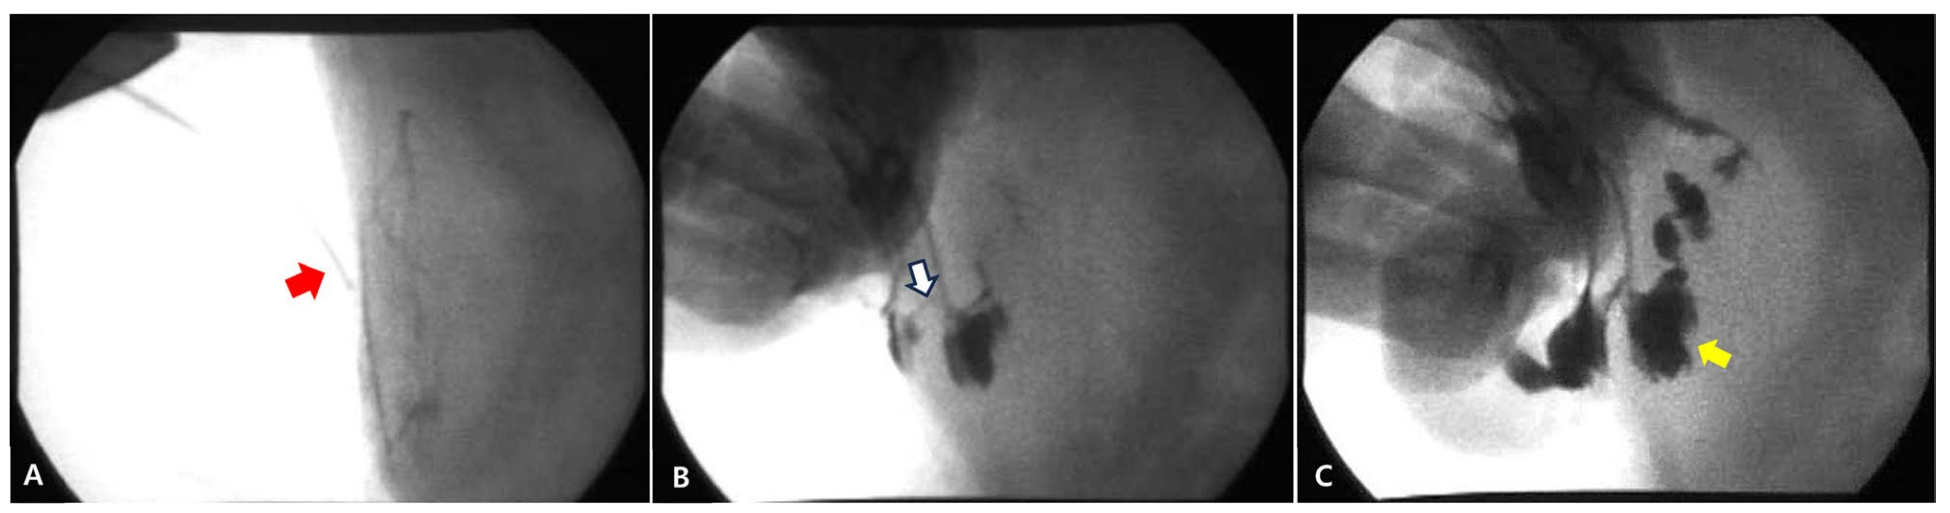

进行了瘘管造影以确定瘘管的起源和通畅性。瘘管造影时,将一根24G套管针插入瘘管,并在透视下缓慢注入约3 mL碘海醇。透视显示造影剂从皮下和腹壁层通过腹壁进入邻近肠腔(下图)。这些发现最终确诊为肠皮肤瘘。尽管建议进行CT以评估肠与腹壁之间的粘连程度,但由于主人的经济限制,未进行该检查。

↑ A. 用于瘘管造影的套管针(红色箭头)已放置。B. 通过皮肤瘘管通道注入碘海醇(白色箭头)。C. 在空肠肠腔内发现碘海醇(黄色箭头)。